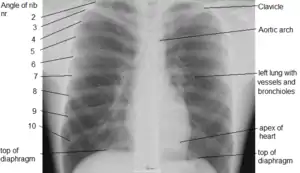

Рентгенограма органів грудної порожнини